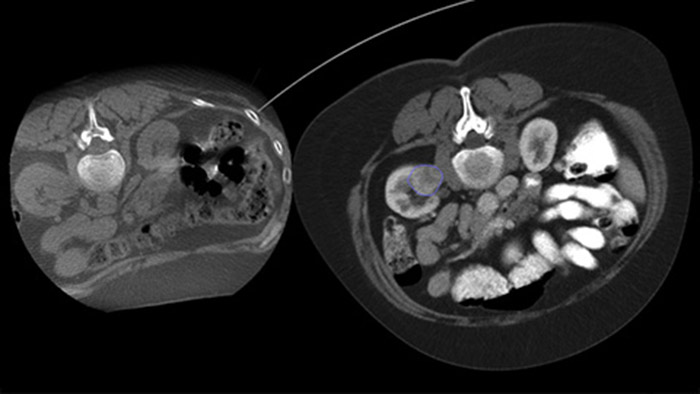

La ablación percutánea (radiofrecuencia, microondas y crioablación) es un tratamiento mínimamente invasivo bien establecido para los tumores de riñón, hígado, pulmón y hueso. Es fundamental definir los límites del tumor y decidir el número óptimo de agujas y la correspondiente trayectoria de estas para poder realizar un tratamiento completo del tumor y no causar daños en el tejido circundante. Navegar con precisión con baja dosis hasta la lesión de interés sin reposicionar la aguja aumenta las posibilidades de éxito y reduce el riesgo de complicaciones de las biopsias o ablaciones. La confirmación del punto final del tratamiento de ablación puede realizarse con imágenes en 3D mientras el paciente sigue en la mesa.

Dual View permite la superposición de una imagen 3D previa al procedimiento (TC/RM/TEP) sobre una THC Dual 3D intraprocedimiento para visualizar mejor las lesiones y acceder a información crítica para la planificación de la trayectoria de la aguja.

Adquiera una THC posterior a la ablación para demostrar la extensión de la cobertura del tumor y confirmar la finalización de su tratamiento.